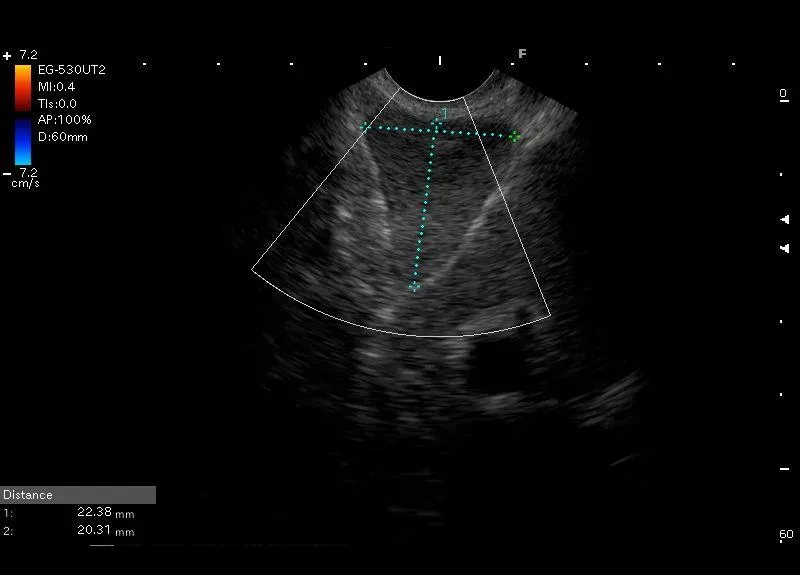

Powiększony węzeł chłonny